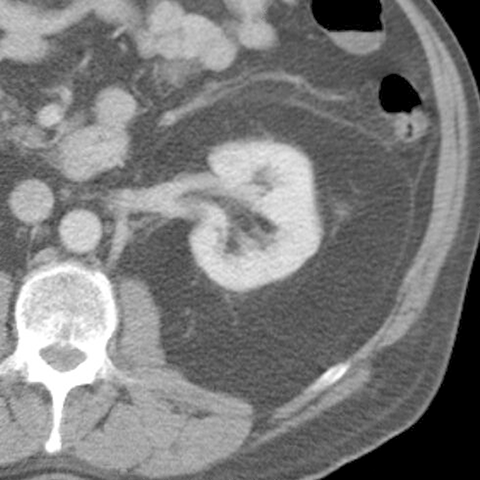

Renal Fascia [2 of 9]